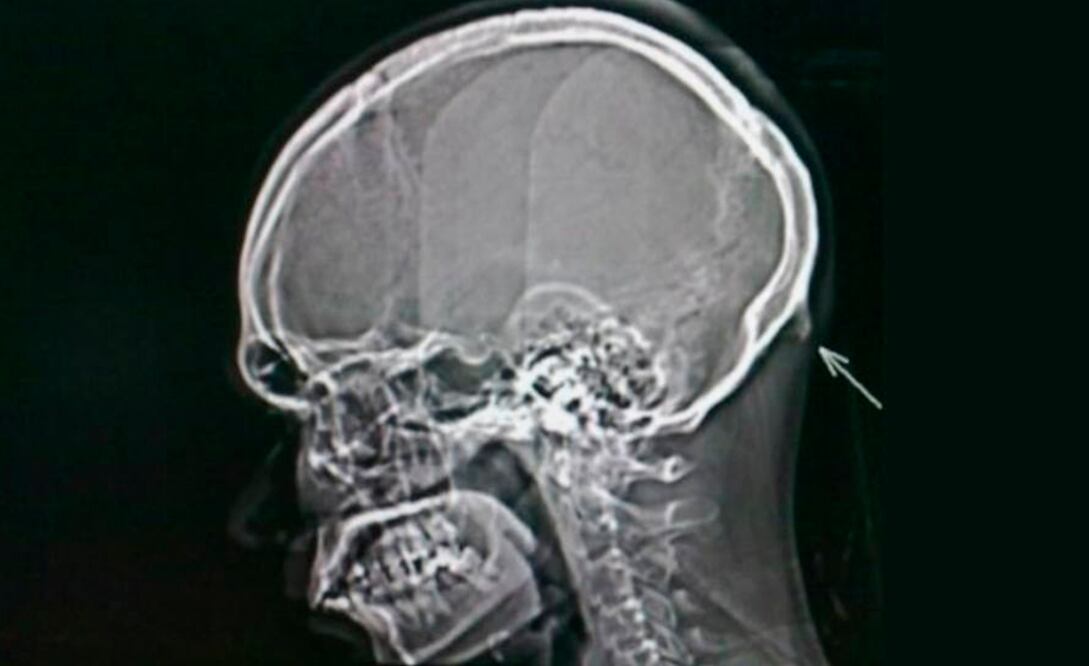

Llamado protuberancia occipital externa; este “cuerno” aparece en la parte posterior de la cabeza, por encima del cuello y, de acuerdo con el doctor Shahar, puede sentirse al tacto, e incluso llega a ser visible en personas calvas.

El investigador descubrió el “cuerno” al revisar a 218 personas de entre 18 y 20 años de edad, en el año 2016. Un 41% de los sujetos muestra revelaron el pequeño pico de más de 10 milímetros, así lo indicó en una entrevista para el medio británico BBC.